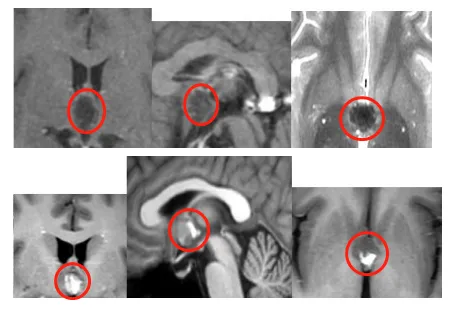

有一种极为特殊的类型,叫做 “真”后交通动脉瘤。动脉瘤的瘤...